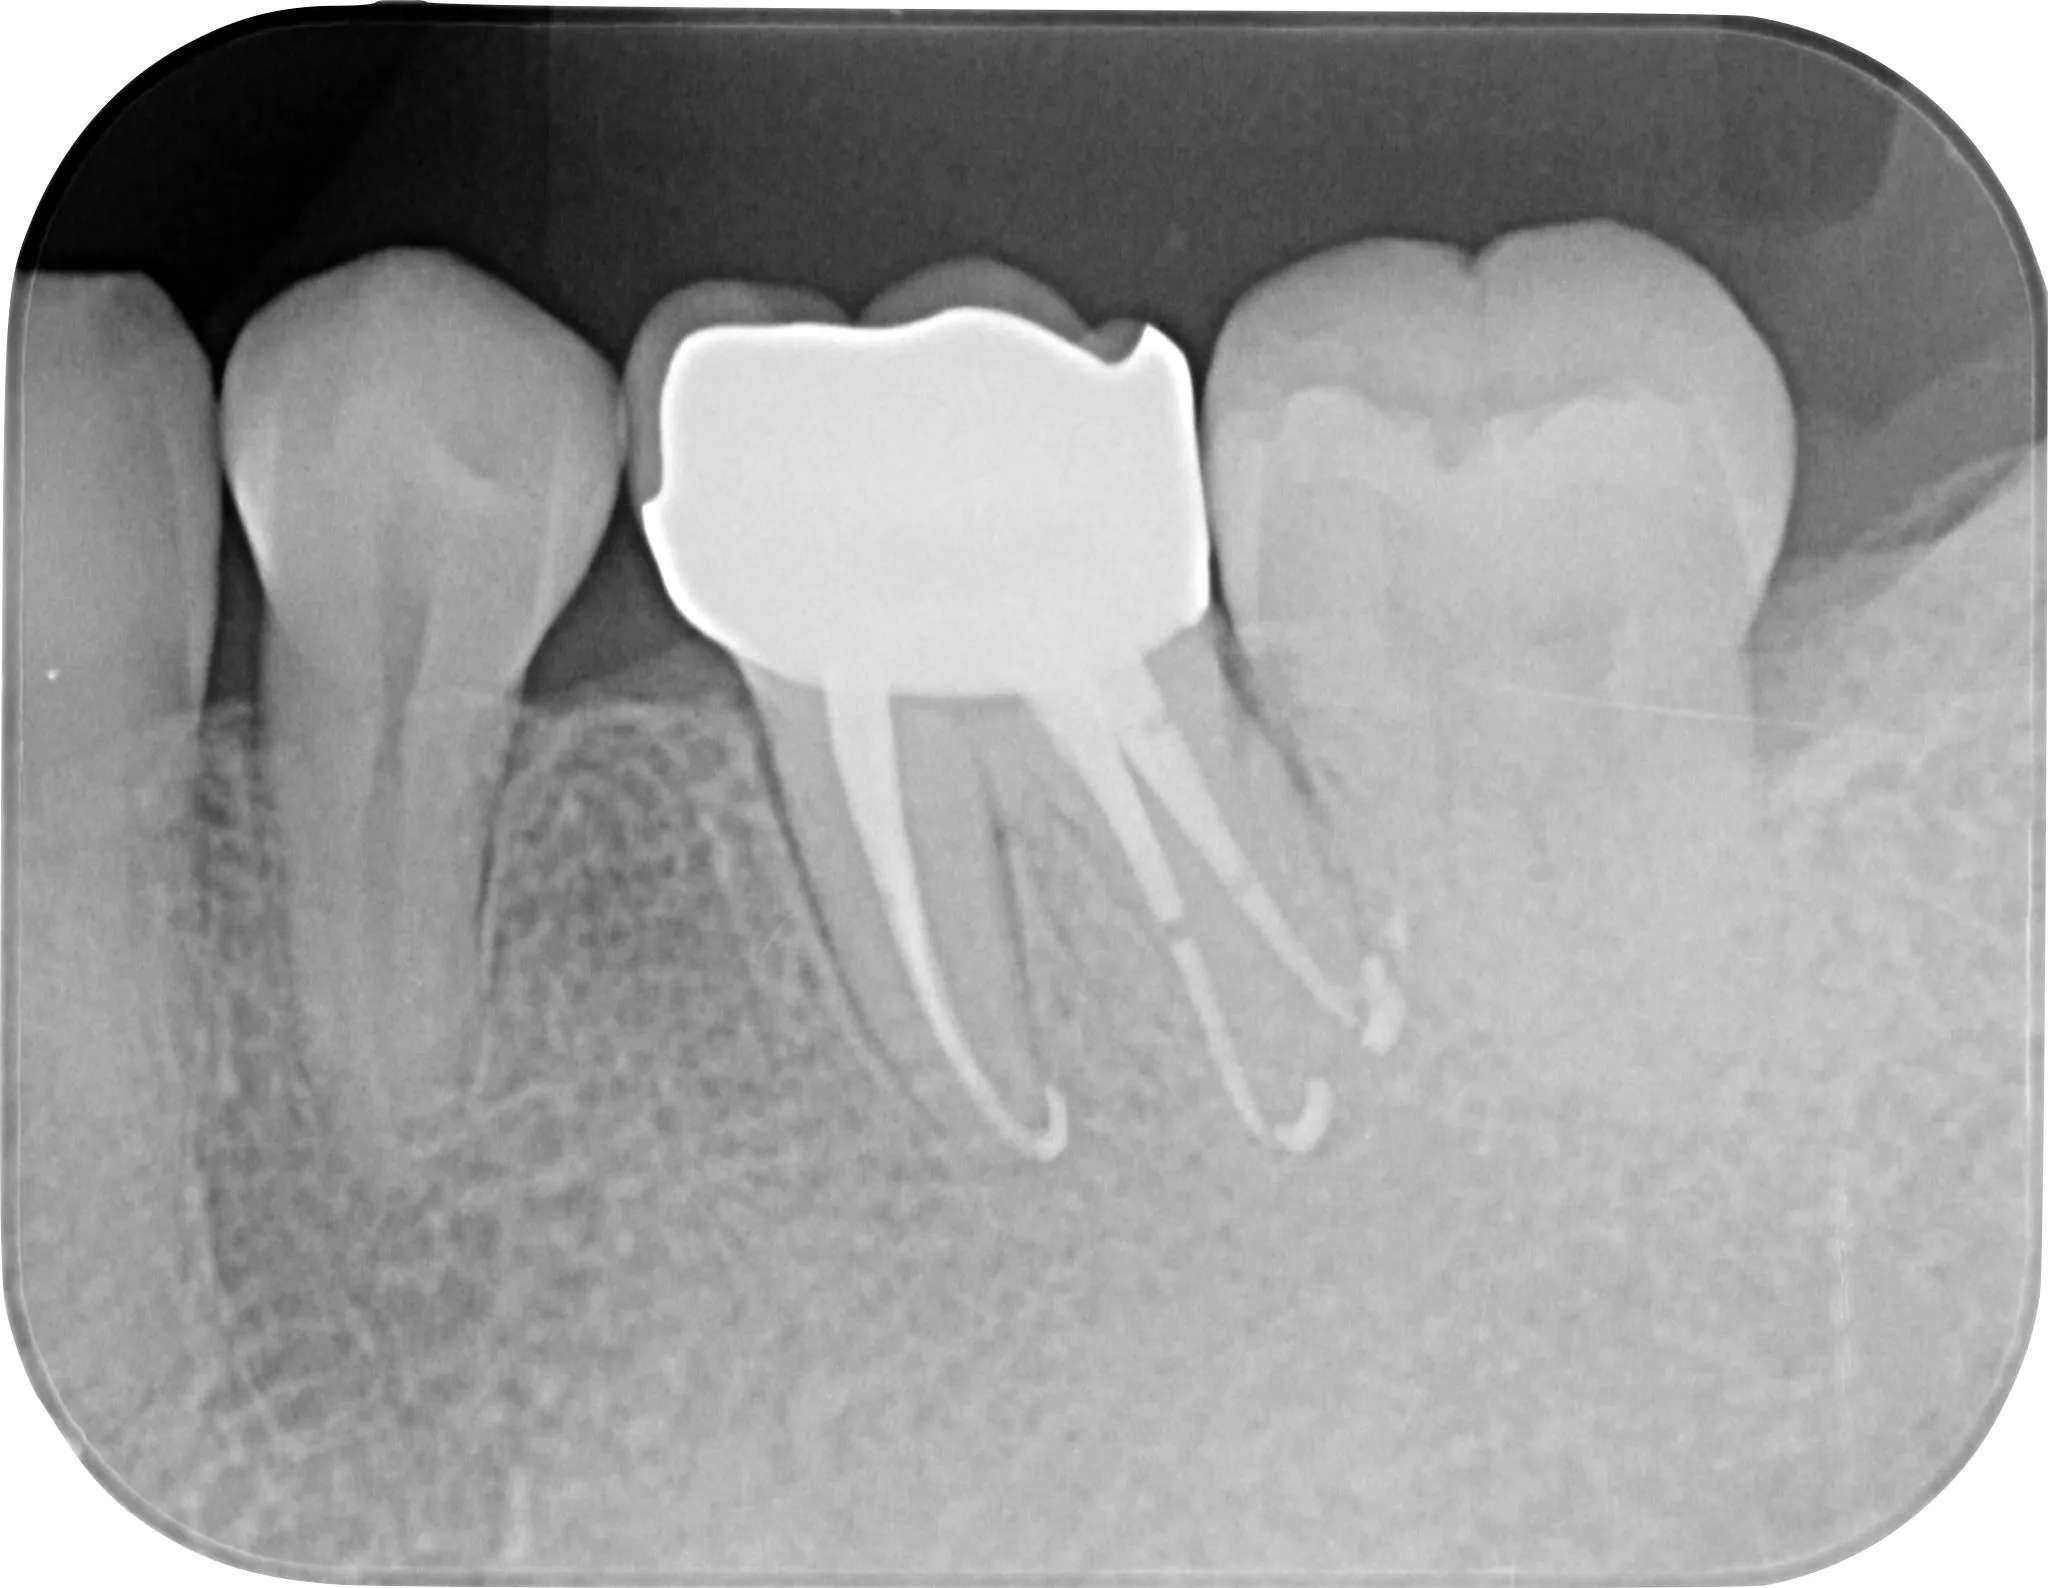

治療後